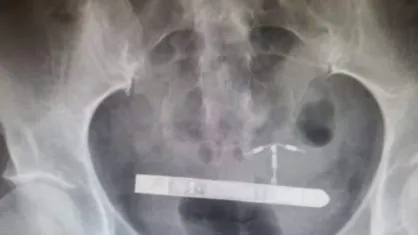

“Nós da equipe médica não conseguimos encontra-lo na vagina”, relembrou o ginecologista Greg Marchand. Em seguida, a mulher passou por um exame de raio x. “Fiquei surpreso quando percebi que ele estava na bexiga da paciente”.

A remoção do objeto foi feita pelo médicos, que compreenderam a entrada do vibrador pela uretra e alojamento ao lado da bexiga. A norte-americana disse que após a recuperação pretende processar a empresa fabricante, “não existe aviso de que isso poderia acontecer” e o “design pequeno e estreito é perigoso”.